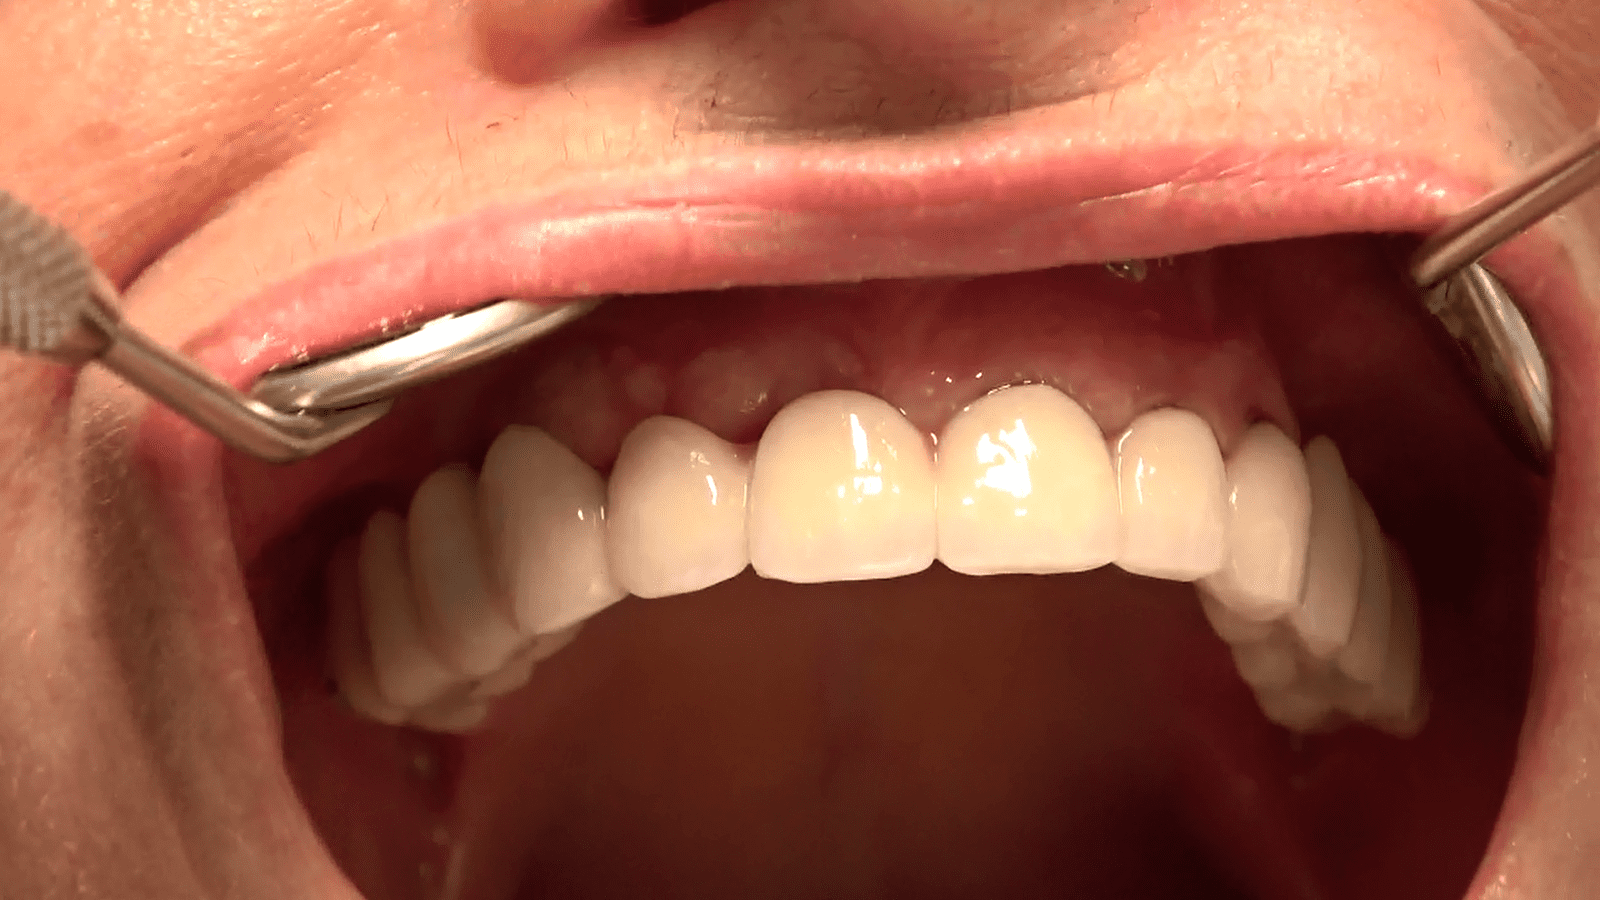

Risultati e Prospettive:

Il paziente, dopo un periodo di recupero relativamente breve, ha ripristinato la funzionalità e l’estetica del sorriso. Questo caso dimostra come l’implantologia sottoperiostea possa essere una soluzione efficace anche per pazienti con atrofia ossea estrema, offrendo risultati duraturi e soddisfacenti.